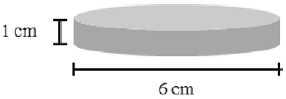

A sensação de um paciente ao ter a campânula de um estetoscópio encostada nele é de que a peça está fria; aos poucos, essa sensação diminui. Considere que essa campânula tenha a forma cilíndrica e seja constituída de uma liga metálica isotrópica com coeficiente de dilatação volumétrico igual 60 × 10-6 °C-1. Considere, ainda, que a peça esteja à temperatura ambiente de 20 °C, tenha diâmetro de 6 cm e espessura de 1 cm, conforme ilustrado na figura abaixo.

Sabendo que o paciente se encontra à temperatura de 38 °C, assinale a opção que apresenta corretamente o acréscimo sofrido pelo raio da peça, em micrômetros, ao entrar em equilíbrio térmico com o paciente.